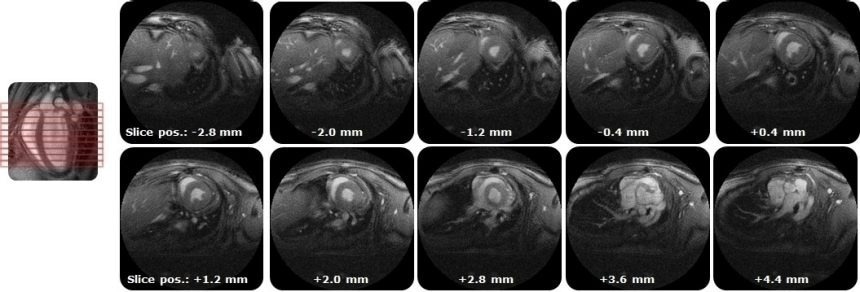

IntraGateUTE with its radial readout enables high quality cardiac cine data in shortest measurement time.

IntraGateUTE, with its radial readout, enables high-quality cardiac cine data in shortest measurement time. Image Credit: Bruker BioSpin Group